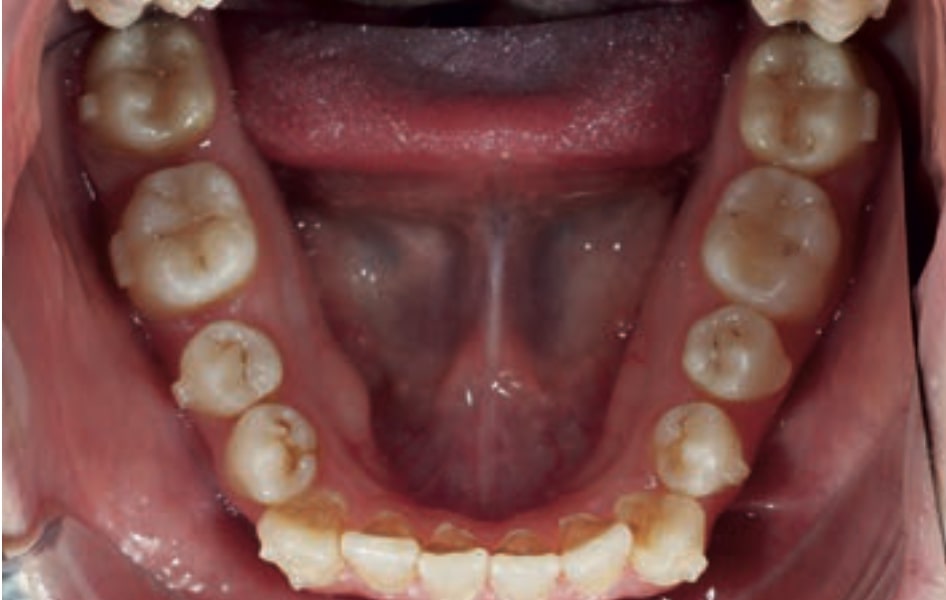

Chief complaint: The patient, a 19-year-old woman, was evaluated to undergo orthodontic treatment using the Angel Aligner Pro system. She presents with a skeletal Class III, mesofacial, with a dental Class III malocclusion and a 2 mm deviation of the lower midline to the left. Teeth 33 and 43 are out of the arch and cortical bone, with a crossbite issue on tooth 33. Fortunately, no functional issues affecting swallowing or breathing have been detected. The patient’s motivation for starting treatment was a general review of her dental and aesthetic health. The soft tissue analysis reveals mandibular protrusion that influences her facial profile. This diagnosis highlights the need for a comprehensive approach to address dental and skeletal misalignments, improving both the patient’s functionality and facial aesthetics.

• Dental Class III, 2 mm deviation of the lower midline to the left. 33 and 43 out of the arch and the cortical bone.

• Crossbite of 33.

• Distalize third and fourth quadrant

• Solve the cross bite of 33.